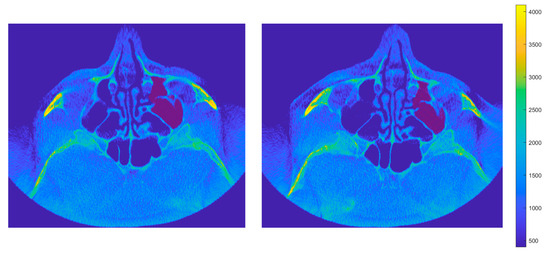

Comparison of Two Methods for Assessing the Maxillary Sinus Volume in Patients with and Without Unilateral Cleft Lip and Palate: A Retrospective Cross-Sectional Study

Background/Objectives: The aim of this study was to compare two methods for maxillary sinus volume measurement, assessing their accuracy. The analysis compared the maxillary sinus volume in patients with unilateral cleft lip and palate (UCLP) and in a non-cleft group, using a manual method and a three-dimensional (3D) semi-automated segmentation method. Methods: The research was conducted according to the STROBE guidelines. Sixty patients were included in this study: thirty patients with UCLP were in the research group, and the control group consisted of 30 patients with no craniofacial deformities. Cone-beam computed tomography (CBCT) was analyzed. The manual maxillary sinus volume was calculated based on its approximation to two geometric shapes based on mathematical formulas using linear measurements that were performed on all sinus CBCT scans in the maximum diameter in three planes. The semi-automatic segmentation method using ITK-SNAP 3D-imaging software version 4.2.2 was used to automatically calculate the maxillary sinus volume of the sinuses. The manually calculated volume was compared with the automatically calculated one, and statistical analysis was performed. Results: The cleft group presented lower values in both the automatic and manually calculated volumes for both the right (automatic: p = 0.49; manual p = 0.009) and left (automatic: p = 0.46; manual p = 0.11) maxillary sinuses than the non-cleft group. The cleft group presented statistically significant higher discrepancies in values between the manual and semi-automatic method than the control group (RMSV p = 0.0011; LMSV p = 0.033; TMSV p = 0.003). Conclusions: The manual method may not reveal the exact anatomical topography of the maxillary sinuses. In UCLP patients, the maxillary sinus anatomy may be more complex. Therefore, a semi-automated method may be more advisable to preserve the accuracy of the measurements. Full article